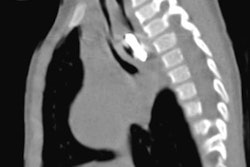

CEM helps show the development of new blood vessels from a pre-existing vasculature that are linked to breast malignancies. This modality also provides morphological information on the lesions, as standard mammography does, and allows areas and lesions to be visualized that show the uptake of contrast media.

Overlapping features of benign and malignant lesions make it challenging to differentiate between the two in low-energy CEM images. This leads to a BI-RADS 4 categorization, meaning core needle biopsy is recommended for further analysis. Current guidelines for CEM in this area are "indecisive," the researchers noted.